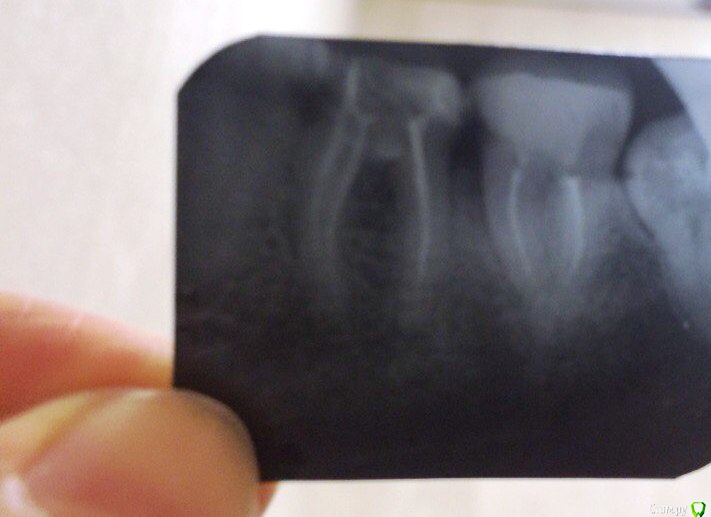

Бендер Опубликовано 11 февраля, 2016 Поделиться Опубликовано 11 февраля, 2016 Качество не только фото не огонь, но и пломбирования каналов Ссылка на комментарий

Stom22 Опубликовано 16 февраля, 2016 Поделиться Опубликовано 16 февраля, 2016 На прикосновение реагирует 6ка - это периодонтит 100% из-за не качественного пломбирования каналов. В области мезиального корня по снимку такое ощущенние, что есть разряжение. Сделайте снимок на визиографе, там качество снимка в разы лучше будет. На холодное может реагировать только 5ка. Проверьте её на наличие скрытых кариозных полостей и пульпита. Ссылка на комментарий